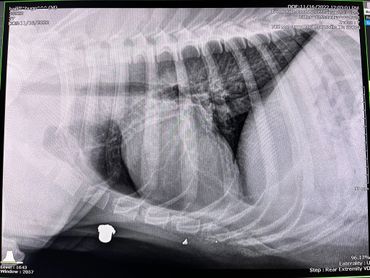

We were working outside, and a couple of our dogs were playing in the yard. It was starting to get dark when we heard a bunch of coyotes followed by a gun shot. We live in the middle of nowhere so these types of things aren’t unusual, but this time the sounds were uncomfortably close. The dogs were quick to come back up to the house, but Hugo was no where to be found. We hollered for him for hours. It was 22 degrees that night, and Hugo hates the cold, but he never came home. We searched the woods for hours the next morning. Nothing. We took to local Facebook groups to find him with no luck. When Shanda came home from work that Tuesday, Hugo was standing at the top of our driveway. He was beat up pretty bad, his hind leg was swollen, overall he seemed ok, but most importantly he was alive! THANK GOD! Jamie took him to the vet the following morning, and we learned that he had actually been shot by a muzzleloader. The bullet entered the back of his hind leg, come out the front of his leg, reentered his stomach, and stopped at his chest. The injury to his leg was too severe for our vet to repair, and with so many other question marks remaining, we had no choice but to amputate. He had lost a lot of blood and was possibly bleeding internally so we had to put the surgery off several days to get his blood count up. He spent eight days at the vet trying to stabilize his body before they were comfortable enough to do the amputation and fix the hernia where the bullet reentered his stomach. The vet was not able to remove the bullet from his chest without fear of it moving further into his chest cavity. A few days after surgery, we finally got to bring our big guy home! He’s doing very well and is adjusting quickly. It’s truly a miracle! We pray that the muscles around the bullet heal and keep the bullet in place to avoid any further complications. Right now we are just thankful that our baby is home and alive!